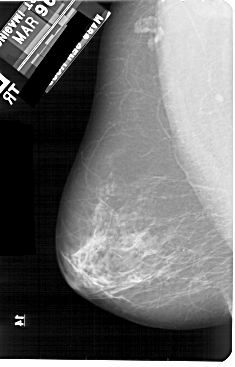

A_1908_1.LEFT_MLO

LEFT_MLO LINES 5491 PIXELS_PER_LINE 3511 BITS_PER_PIXEL 12 RESOLUTION 43.5 NON_OVERLAY